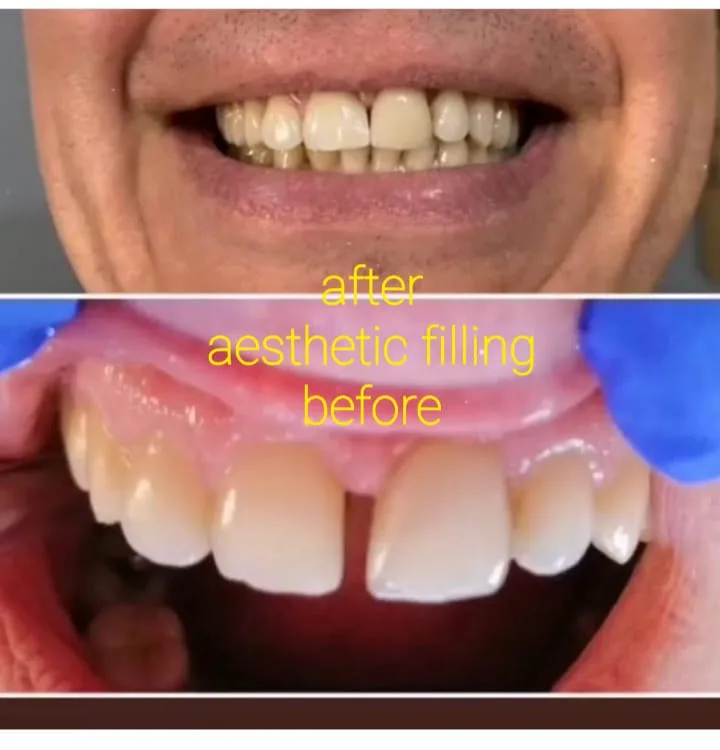

✅ Эстетическая стоматология: отбеливание и реставрация